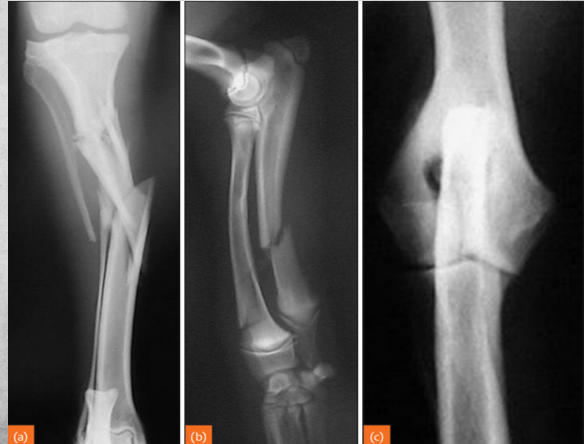

Fractures can be either..

primary or secondary.

Also, complete or incomplete. (periosteum can be intact with fracture line otherwise).

Left image: gunshot caused fracture.

Right image: osteosarcoma caused fracture.

identify

incomplete fractures

identify left to right

left to right:

Transverse fracture

Oblique fracture

Spiral fracture